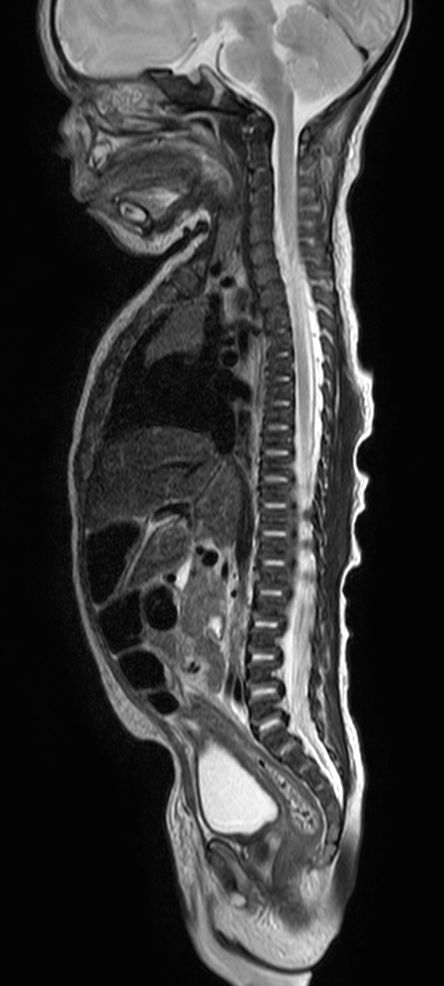

Pediatric Total Spine with spina bifida

Neonatal patient, 5 days old, with spina bifida